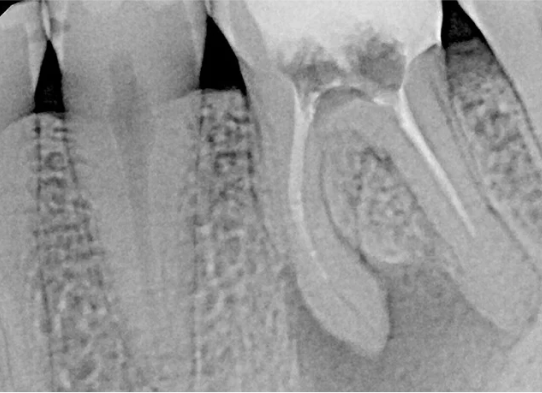

Po zakończonym leczeniu kanałowym, wykonujemy kontrolne zdjęcie RTG. Pozwala ono na natychmiastową ocenę jakości wypełnienia kanałów korzeniowych i potwierdzenie skuteczności przeprowadzonego zabiegu. Dla nas leczenie kanałowe Opole to synonim precyzji i pewności.

Na podstawie zdjęcia rentgenowskiego określa się kształt i długość kanału bądź za pomocą specjalnego urządzenia mierzy się jego długość. Potem lekarz otwiera wejścia do kanału, chroniąc ząb koferdamem, czyli specjalną gumą, zapewniającą sterylność oraz chroniącą przed środkami chemicznymi służącymi do oczyszcza-nia kanału. Używa się do tego zarówno specjalistycznego sprzętu, jak i nowo-czesnych mikroskopów, pozwalających na uzyskanie dokładnego obrazu leczone-go zęba. Ostatnią czynnością jest wypełnienie materiałem światłoutwardzal-nym i zabezpieczenie zęba przed dostaniem się i rozwojem bakterii mogących wywołać wtórny stan zapalny.

Przed rozpoczęciem leczenia kanałowego kluczowa jest dokładna diagnostyka. Zazwyczaj wykonujemy kontrolne zdjęcia RTG, a czasem nawet kilka, aby precyzyjnie ocenić stan zęba i otaczających go tkanek. W bardziej skomplikowanych przypadkach możemy zlecić wykonanie tomografii komputerowej (CBCT) dla uzyskania trójwymiarowego obrazu.

Nasza diagnostyka to nie tylko cyfrowe zdjęcia RVG (radiowizjografia), które ograniczają dawkę promieniowania i dają natychmiastowy obraz. W skomplikowanych przypadkach kierujemy pacjentów na tomografię komputerową CBCT, która daje trójwymiarowy obraz struktur zębowych i kostnych, co jest nieocenione przy planowaniu trudnego leczenia kanałowego lub ponownego leczenia endodontycznego.